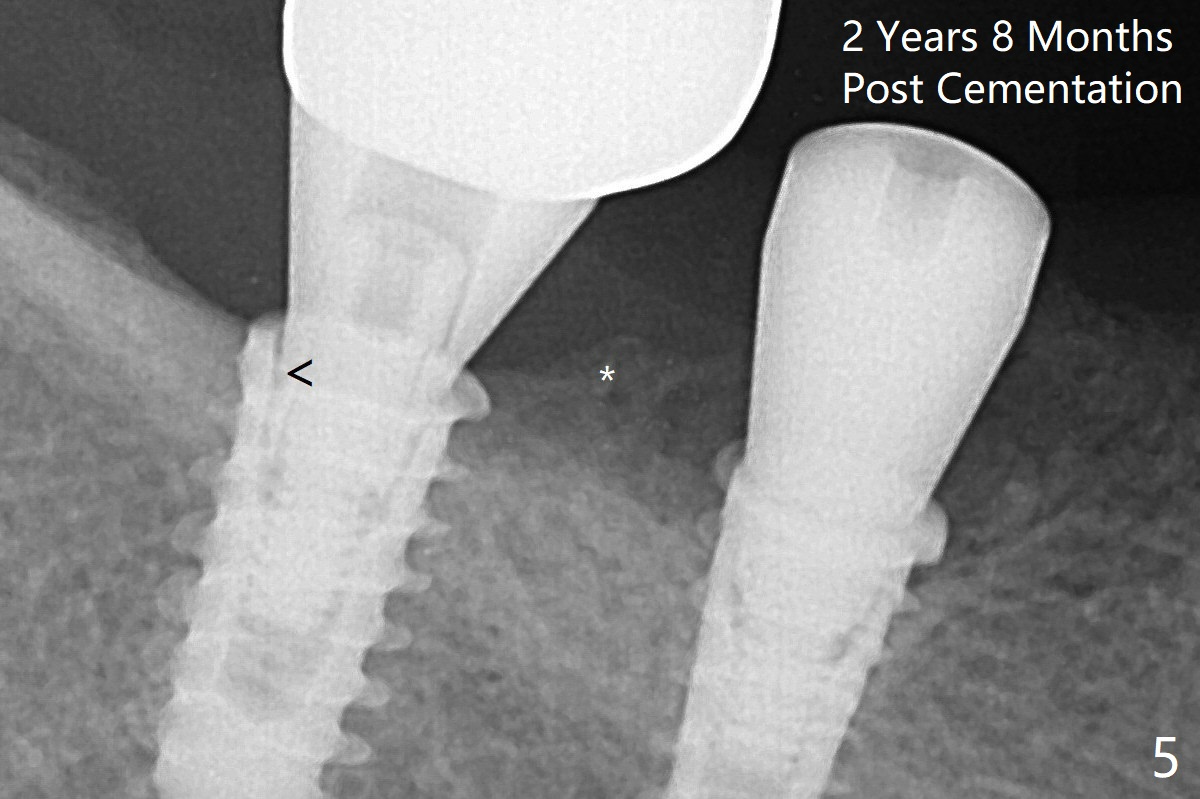

Note bone growth, especially at #30, 2.5 and 4 months postop (Fig.3,4). In fact the abutments are incompletely seated. The crown of #30 is loose with foul smell 2 years 8 months post cementation. It is painful to reinsert the crown/abutment after proximal reduction. A healing abutment is placed (Fig.5). When the incompletely seated abutment at #31 is removed, there is also smell. After separation from the crown, the abutment of #31 returns to the site with change in insertion position, while a smaller abutment has to be used at #30 (Fig.6) due to use of the small healing abutment earlier (Fig.5). A good piece of news is the presence of the bone between the implants (Fig.5,6 *), which contributes to interimplant papilla.